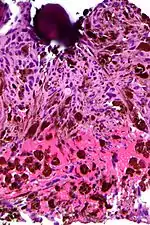

Micrograph of psammoma body in the centre of the field in a meningioma of brain. H&E stain.

A psammoma body is a round collection of calcium, seen microscopically. The term is derived from the Greek word ψάμμος (psámmos), meaning "sand".

Psammoma bodies usually have a laminar appearance, are circular, acellular and basophilic.